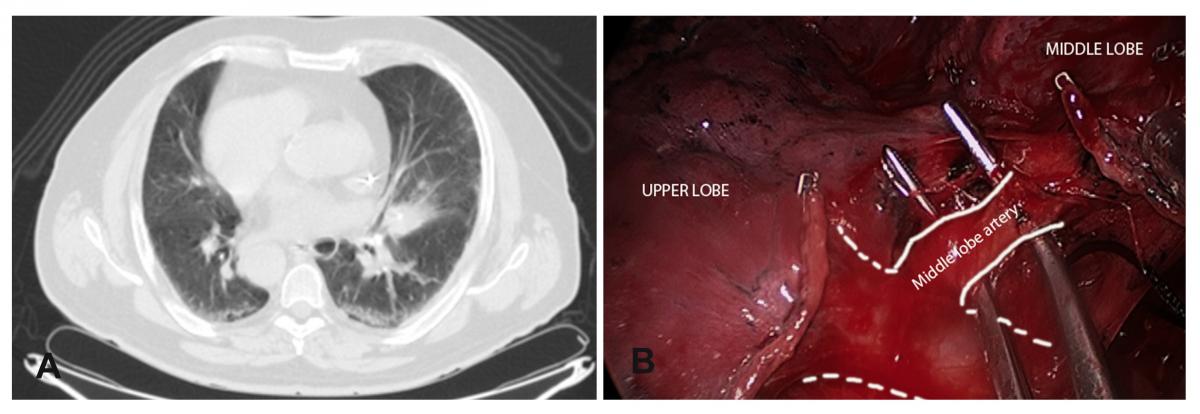

A 3cm mass was located in the middle lobe (Fig. 2A), too large and deep to perform a wedge resection so a middle lobectomy (Fig. 2B) with complete lymphadenectomy was performed (paratracheal and subcarinal space). A single chest tube was placed in the posterior part of the incision.